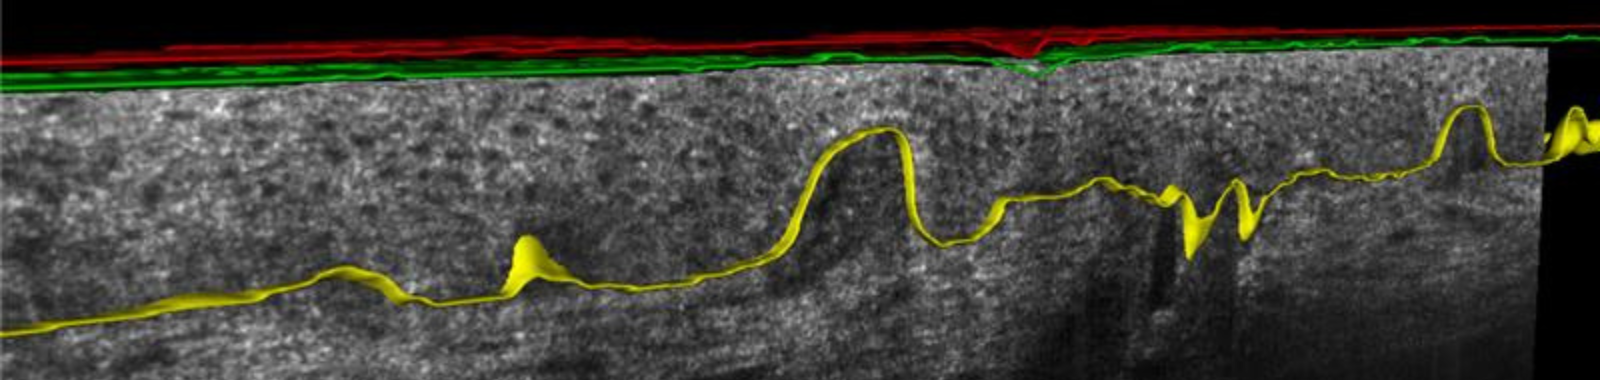

Eurofins BIO-EC a récemment intégré la tomographie par cohérence optique confocale en champ de ligne (LC-OCT, Line-field Confocal Optical Coherence Tomography) à son portefeuille, renforçant ainsi ses capacités d’imagerie in vivo pour l’évaluation de l’efficacité des produits cosmétiques. Initialement validée en oncologie dermatologique, la LC-OCT suscite aujourd’hui un intérêt croissant en sciences cosmétiques grâce à sa capacité à visualiser la microarchitecture de la peau de manière non invasive et avec une résolution proche de l’histologie.

La LC-OCT permet une imagerie en temps réel et à haute résolution de l’épiderme et du derme superficiel, facilitant des analyses qualitatives et semi-quantitatives détaillées des modifications structurelles induites par les produits cosmétiques. Cette approche est particulièrement pertinente pour les comparaisons avant/après ainsi que pour le suivi des processus de remodelage dermique après application topique.

D’un point de vue biologique, cette technique est particulièrement adaptée à l’étude du derme papillaire, où se situent principalement les fibroblastes métaboliquement actifs ainsi qu’un renouvellement dynamique du collagène. À l’inverse, le derme réticulaire plus profond contient des fibres de collagène plus épaisses et plus structurales, présentant une moindre réactivité. La LC-OCT offre ainsi un éclairage pertinent sur l’architecture du derme superficiel, zone où de nombreuses allégations cosmétiques sont susceptibles de se manifester.